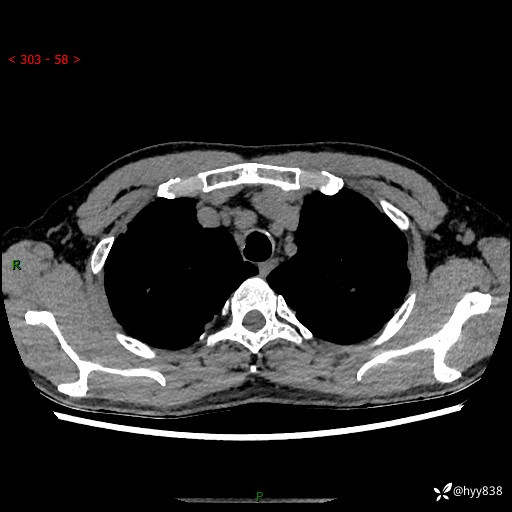

中年男性,咳嗽咳痰1月余。细看:肺、肺门、气管,貌似都有问题---(有结果)

现病史:患者于1个月前受凉后出现间断性咳嗽,伴白色泡沫样痰,无发热寒战、咯血、胸痛胸闷、恶心呕吐、呼吸困难等特殊不适,起初未予特殊处理,后患者就诊当地中医医院,查胸部CT提示支气管炎并双肺感染性病变,经抗感染(哌拉西林舒巴坦),止咳化痰(溴己新、三拗片)等治疗后,患者自诉咳嗽咳痰症状较前缓解,未诉发热等其他特殊不适,近期复查CT提示“肺部感染灶未见消退,双侧肺门增大,双肺散在小结节”,今为求进一步诊治,前来我院就诊,门诊以“肺部感染”收住入院。 患者自起病来精神、食欲、睡眠尚可,大小便正常,体力、体重无明显变化。

胸部CT平扫+增强(两期)